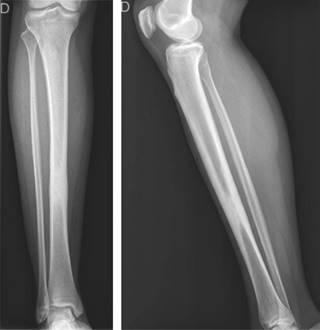

Se realizaron radiografías que demostraron una lesión intraósea diafisiaria única, de localización central, con bordes definidos, periostio engrosado pero sin interrupción y sin signos de malignidad. No se observó afectación de los tejidos blandos ni destrucción ósea adyacente (Figura 1). La resonancia magnética confirmó los hallazgos descritos; la lesión se caracterizó como inespecífica, con apariencia esclerosa y ocupación de toda la cavidad medular, con engrosamiento de ambas corticales (Figura 2). Se realizó una gammagrafía ósea que demostró una posible reacción osteogénica avanzada con evidencia de patología inflamatoria secundaria a destrucción ósea. Se realizó una biopsia incisional cerrada, que descartó lesiones infecciosas o neoplásicas.

Figura 1: Radiografías anteroposterior y lateral de pierna derecha que muestran la lesión intraósea diafisaria.